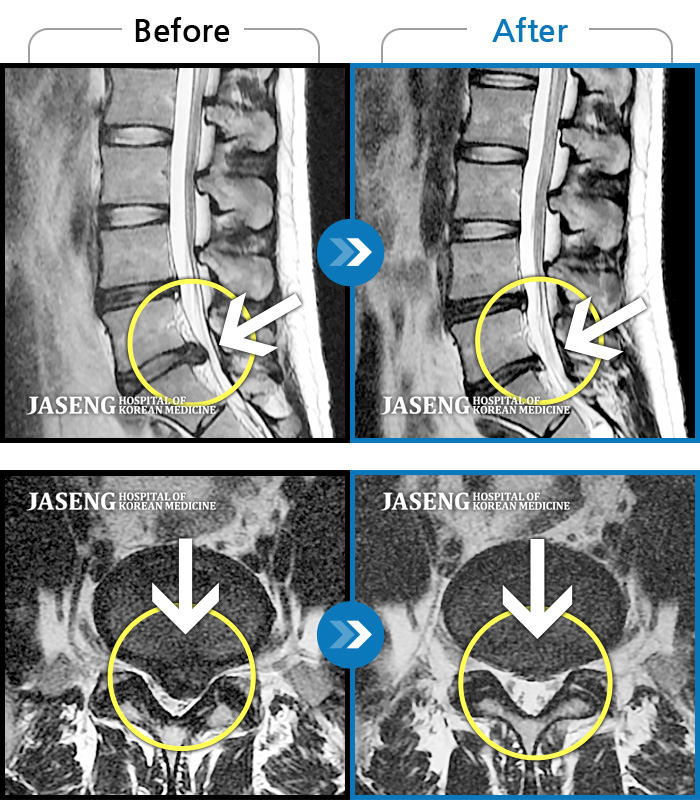

허리디스크 때문에 고생했는데

김유진 원장님의 침치료와

추나요법으로 많이 호전되었습니다

수술을 해야 하는 상황이었는데 자생 한방 병원의 김유진 원장님 덕분에 현재 수술없이 잘 치료를 받고 있습니다.

처음에 수술없이 완쾌할수 있을까 걱정을 많이 했지만 지금은 완쾌할수 있을거랑 희망을 가지고 통원치료를 받고 있습니다.

앉아 있지도, 걷지도 못할 정도로 허리가 아팠었는데 두달 간 김유진 원장님의 치료를 받고 허리 통증이 없어 졌습니다. 치료할 때마다 제가 질문을 많이 했었는데 이 부분에 대해서도 정말 친절하게 답변해 주셨어요. 오히려 너무 상세하게 길게 말씀해 주셔서 제가 다 부담스러울 정도로 말이죠 ㅋㅋㅋ 원장님 치료 덕분에 허리가 낫게 되어 너무 다행이에요!감사합니다!